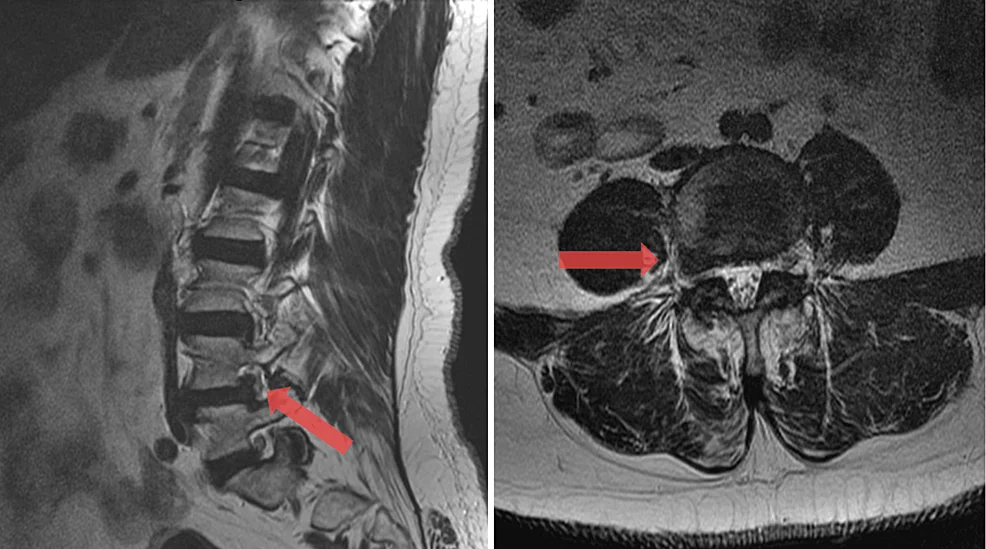

- MRI οσφυϊκής μοίρας με σκιαγραφικό – δείχνει τη νέα κήλη, τη θέση της (κεντρική, παρακεντρική, τρηματική, εξωτρηματική), τη σχέση με τις ρίζες και τυχόν μετεγχειρητικές ουλές.

Στις υποτροπές, η λεπτομερής μελέτη των παλαιών και νέων απεικονίσεων βοηθά να διακριθεί αν πρόκειται για πραγματικά νέα κήλη, ουλώδη ιστό, εκφυλισμό γειτονικού επιπέδου ή συνδυασμό.